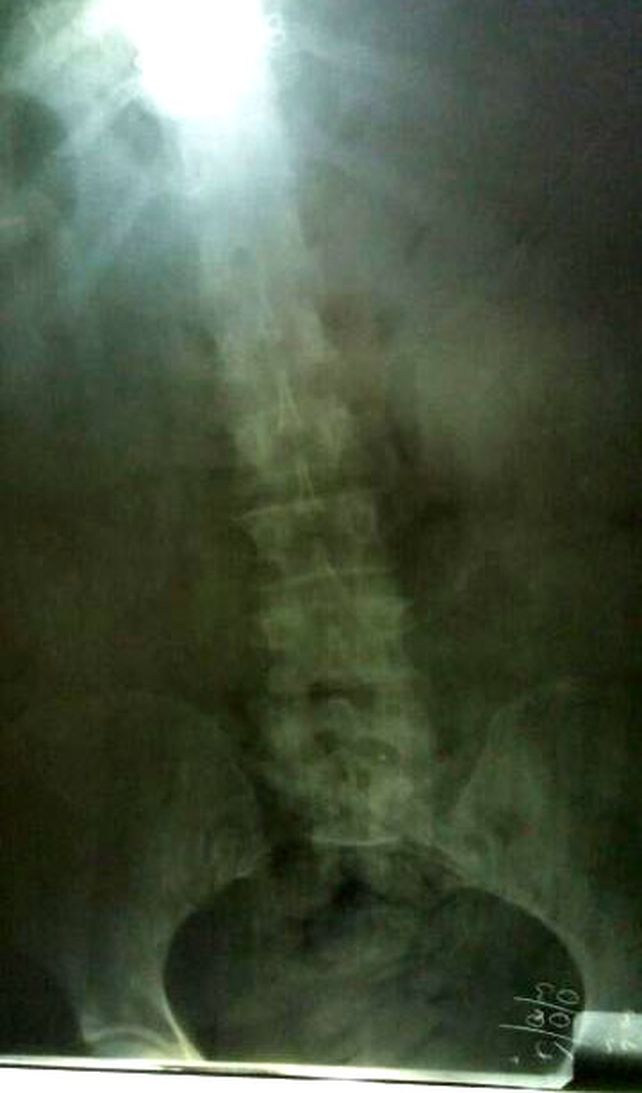

Allí le tomaron placas radiográficas; y en tales imágenes se registró la presencia de objetos extraños (cápsulas de cocaína) en el tracto intestinal de su cuerpo. Ante esa situación, la ciudadana boliviana quedó internada para preservar su salud, y además, para la evacuación total de la ingesta de las cápsulas.